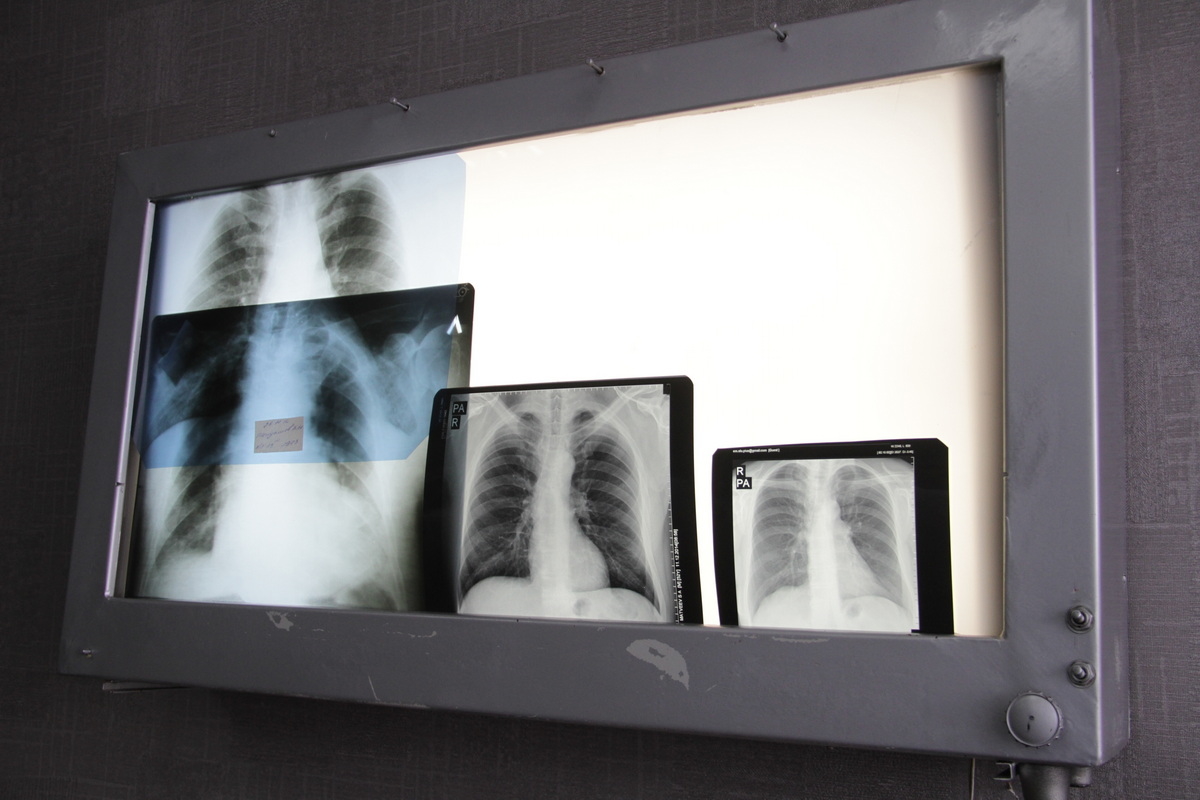

За 10 месяцев в Восточно-Казахстанской области выявлено 228 новых случаев рака лёгких. Заболевание занимает третье место среди онкопатологий региона, передает корреспондент YK-news.kz.

Наибольшая заболеваемость отмечается в возрастной группе 60–69 лет, сообщила заместитель директора Центр онкологии и хирургии ВКО Бекзат Мукадиева.

Отмечается улучшение ранней диагностики: на I–II стадиях выявлено 65 случаев (31,3%), что на треть больше, чем годом ранее. Количество пациентов с IV стадией снизилось до 33.